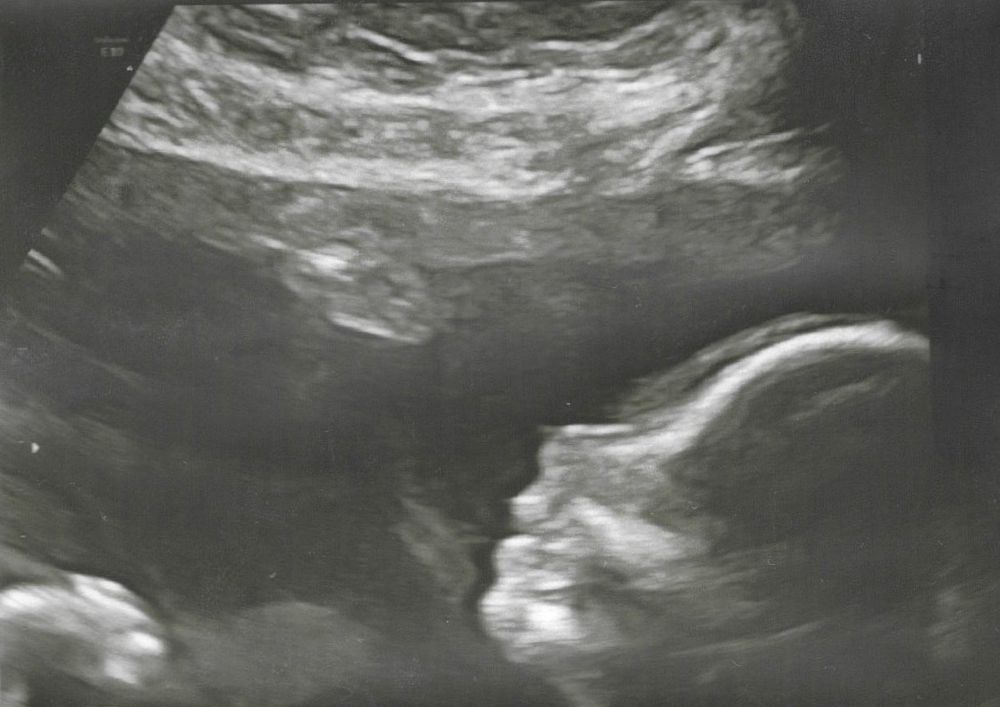

19+2 (18+5?😂) УЗИ

Мой ВикторПо пм 18+5, по первому скринингу 19+2

По фетометрии на сегодняшний день 18+5, как по пм)

Мальчик, уже 100%😁